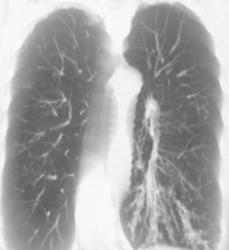

Hypervascular Lung and Liver Metastases From Renal Cell Cancer